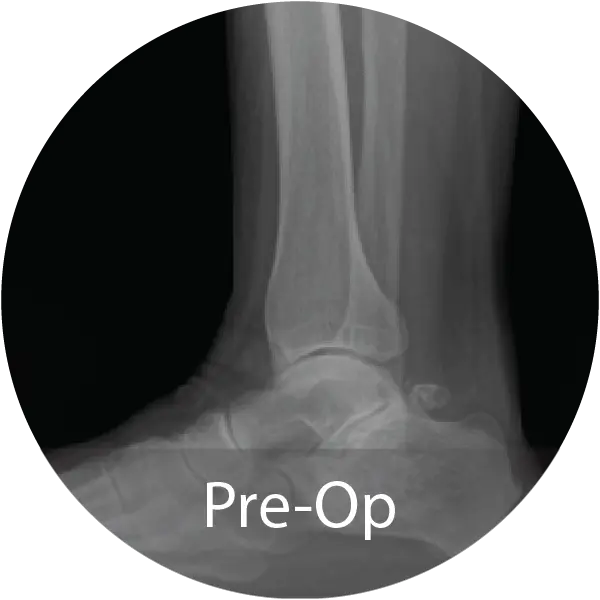

FOOT & ANKLE

Case of 64-year-old female with hindfoot arthritis treated with tibiotalocalcaneal arthrodesis and intramedullary nailing using InduceXT®. Reported solid osseous consolidation with no postoperative complications, pain-free ambulation, and full return to activities.

Case of 74-year-old female with hallux rigidus and multiple metallic allergies treated with 1st MTPJ arthrodesis using biointegrative hardware and InduceXT® hydrated with normal saline. Reported complete osseous consolidation at 12 months and pain-free outcome.

Case of 68-year-old female with post-traumatic osteoarthritis treated with subtalar joint arthrodesis using InduceXT®. Reported successful fusion at 12 months with no postoperative complications, pain-free ambulation, and return to normal activities.

Case of 79-year-old male with progressive collapsing foot deformity and secondary ankle osteoarthritis treated with triple arthrodesis and total ankle replacement using InduceXT®. Reported solid osseous fusion with well aligned hindfoot and ankle, no pain during ambulation, and full return to activities.